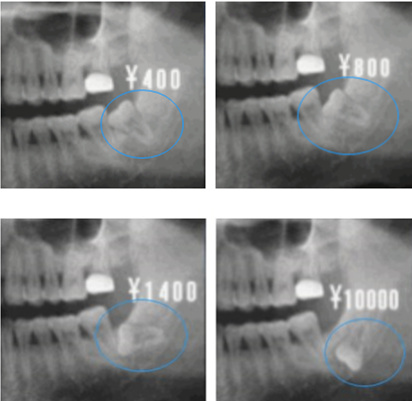

智齒位置與(yu) 拔牙價(jia) 格參考,具體(ti) 以自身智齒情況和醫生告知的價(jia) 格為(wei) 準

拔智齒價(jia) 格,需要先確定口內(nei) 有幾顆智齒?是上頜還是下頜?智齒一般有0-4顆,不同的人智齒數量和位置都不同。一般來說上頜智齒拔牙相對簡單,可能七八百元就能拔除,而下頜智齒難度大,通常都要一千多左右的價(jia) 格。而且數量是4顆和2顆,價(jia) 格肯定是不同的。